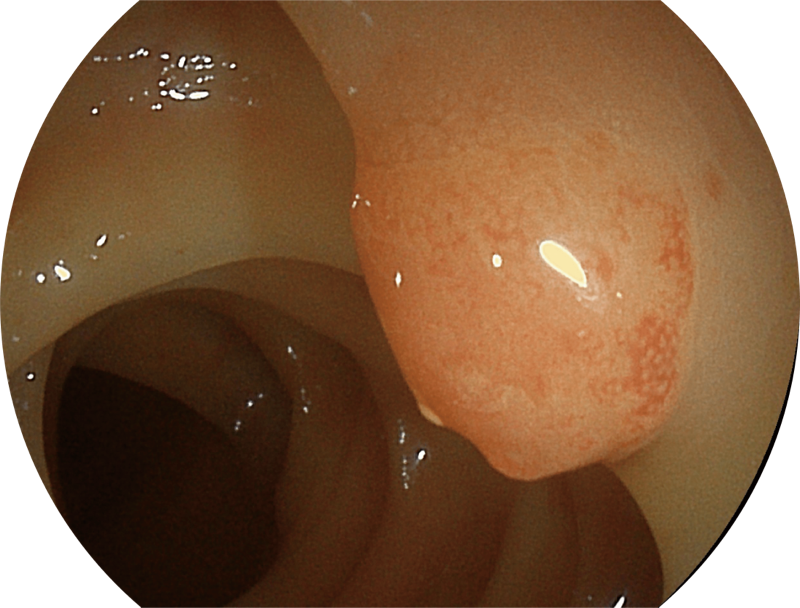

百万级像素高清传感器,1080P全高清视频信号输出,图像清晰。

能够凸显黏膜浅层和中层血管轮廓,适用于中、远景观察下的病灶识别和早癌筛查。

能够凸显黏膜浅层血管轮廓和黏膜表面微结构,适用于中、近景观察下的早癌精确诊断。

弯曲角度大,方便观察食管下段贲门、胃底部等难以观察到的部位,减少盲区。